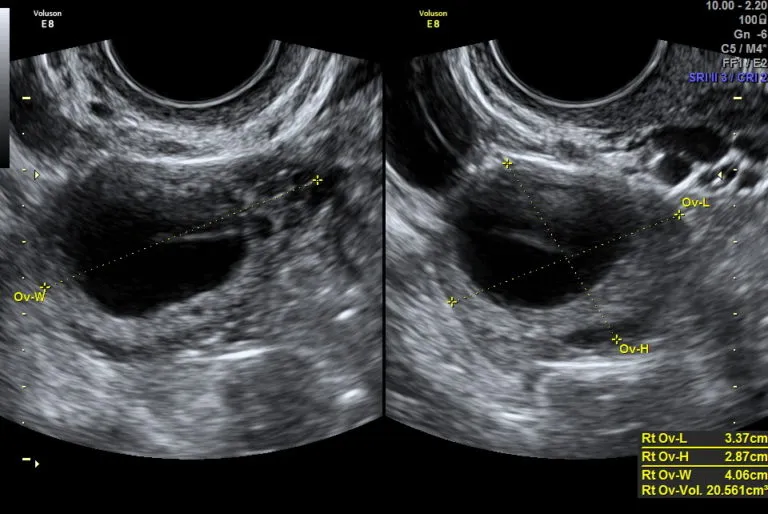

Monitoring cyklu u ginekologa: Kiedy USG staje się niezbędne?

Monitoring cyklu za pomocą ultrasonografii (USG) u ginekologa to najbardziej precyzyjna metoda śledzenia owulacji. Lekarz, wykonując serię badań USG w różnych fazach cyklu, może dokładnie obserwować wzrost pęcherzyków Graafa w jajniku, oceniać grubość endometrium oraz moment pęknięcia pęcherzyka i uwolnienia komórki jajowej. Ta metoda jest niezbędna w sytuacjach, gdy starania o ciążę nie przynoszą efektów przez dłuższy czas, przy nieregularnych cyklach, w przypadku zaburzeń hormonalnych lub podczas leczenia niepłodności. Daje ona najpełniejszy obraz funkcjonowania jajników i macicy.